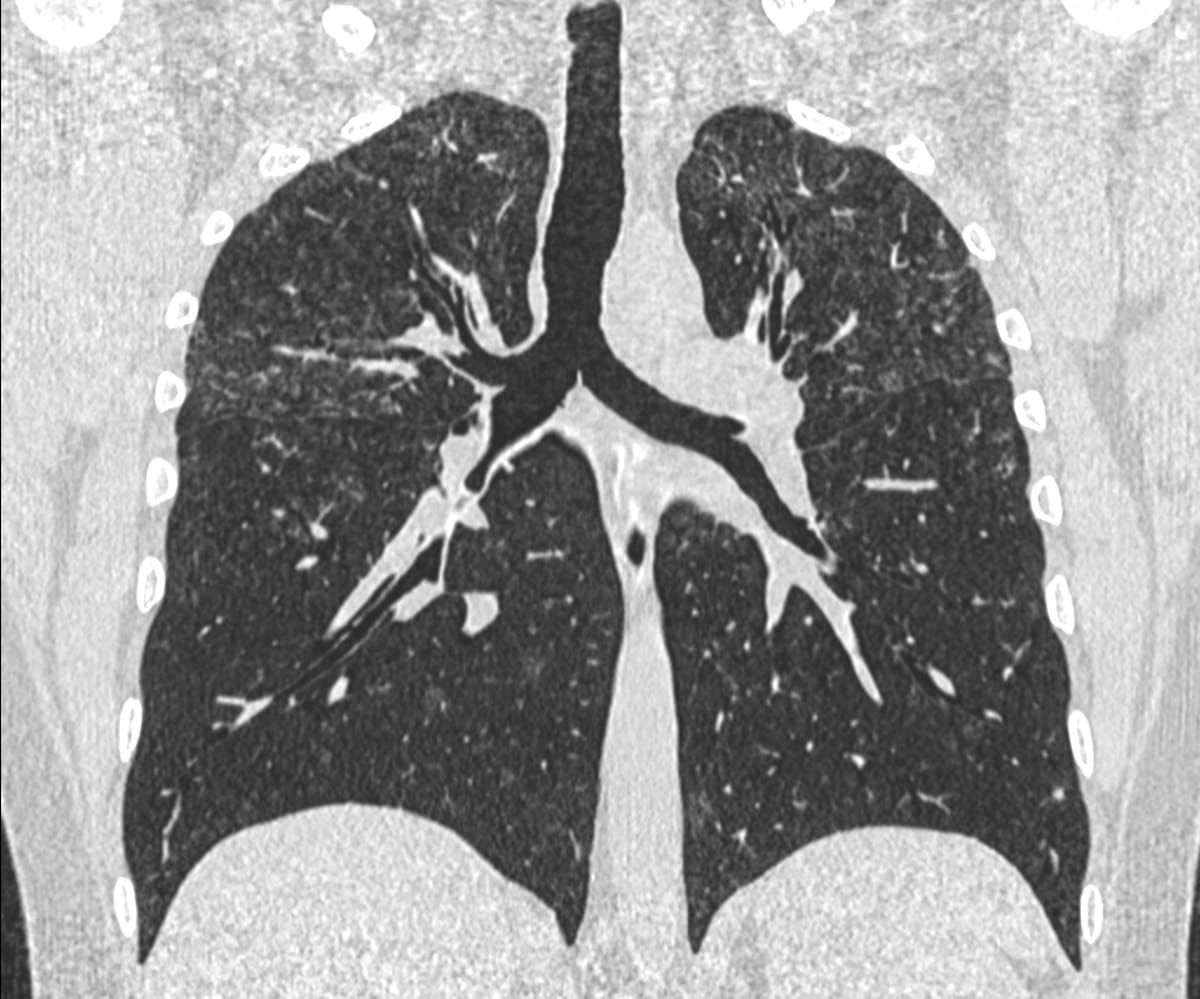

64-years old with rheumatoid arthritis on treatment had dyspnea. He was a 15-pack years smoker who had stopped 10 years ago. He was known to have ILD since 2023 and was on anti-fibrotics.